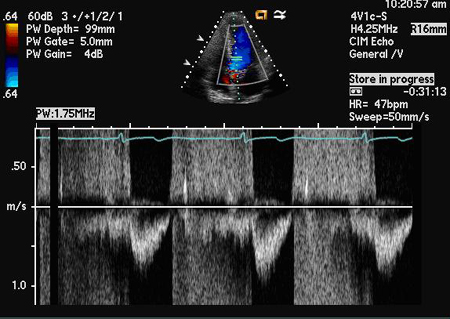

Doppler de onda pulsada

Exame

À medida que a RA se agrava, ocorre um maior grau de reversão de fluxo e a reversão do fluxo holodiastólico indica RA grave; o Doppler de onda pulsada pode quantificar este efeito pela avaliação do volume sistólico regurgitante e da área eficaz do orifício regurgitante.

A reversão do fluxo diastólico é medida na aorta descendente a partir de uma posição supraesternal da sonda.[Figure caption and citation for the preceding image starts]: Doppler de onda pulsada do jato regurgitanteDos acervos Dr. Sanjeev Wasson e Dr. Nishant Kalra; usado com permissão [Citation ends].

O volume sistólico regurgitante pode ser calculado subtraindo-se o volume sistólico para diante, que pode ser determinado na valva mitral, do volume sistólico total (valva aórtica). Tanto o volume sistólico regurgitante quanto a fração regurgitante podem ser calculados dessa forma.

A área eficaz do orifício regurgitante é outra medida para avaliar a gravidade da RA e pode ser calculada dividindo-se o volume sistólico regurgitante pela integral de tempo da velocidade do jato da RA avaliada por Doppler de onda contínua.[24]

Resultado

detecção e quantificação do fluxo holodiastólico reverso